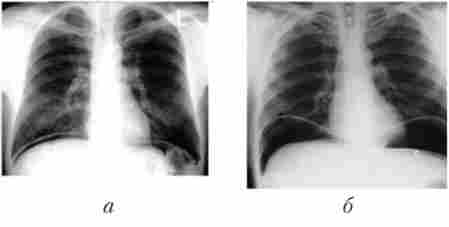

Достовірна ознака перфоративної виразки - вільний газ в черевній порожнині, що можна виявити при оглядовій рентгенографії живота у вертикальному положенні хворого. У цьому випадку вільний газ визначається під діафрагмою (рис. 12.2, а). Якщо хворий не може прийняти вертикальне положення в зв'язку з важким станом, рентгенологічне дослідження живота йому виконують в положенні на лівому боці (рис. 12.3).

Оглядова рентгенографія живота хворого перфоративного виразкою (положення стоячи)

Мал. 12.2. Оглядова рентгенографія живота хворого перфоративного виразкою (положення стоячи):

а - газ під діафрагмою; 6 - збільшення обсягів газу під діафрагмою після фиброгастродуоденоскопии

Якщо при клінічній картині перфоративної ГДЯ вільний газ в порожнині очеревини не виявляється, хворому виконується фіброгастродуодено- скопия (ФГДС). При цьому виявляється сама виразка, уточнюються її характер і локалізація, розміри, іноді в дні виразки видно зміщується при диханні стінка сусіднього органу, а після ендоскопії на повторних оглядових рентгенограмах живота виявляється пневмоперитонеум (див. Рис. 12.2, б).